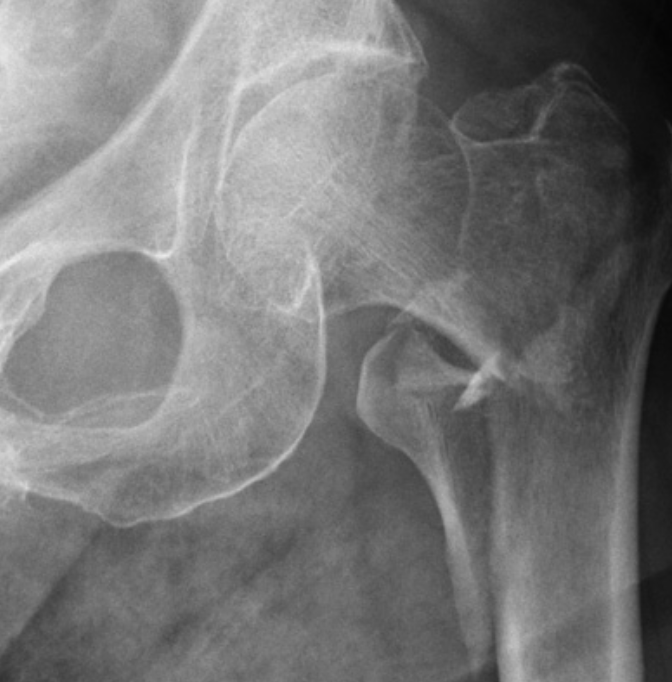

Describe the type of fracture depicted [1]

Intertrochanteric fracture

* A fracture line runs between the trochanters

* There is comminution with separation of the lesser trochanter

* Note the fracture does not involve the femoral neck